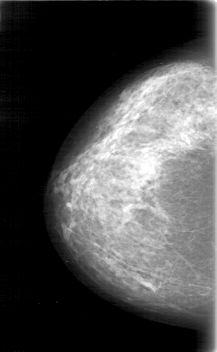

D_4082_1.RIGHT_CC

RIGHT_CC LINES 5266 PIXELS_PER_LINE 3241 BITS_PER_PIXEL 12 RESOLUTION 43.5 NON_OVERLAY